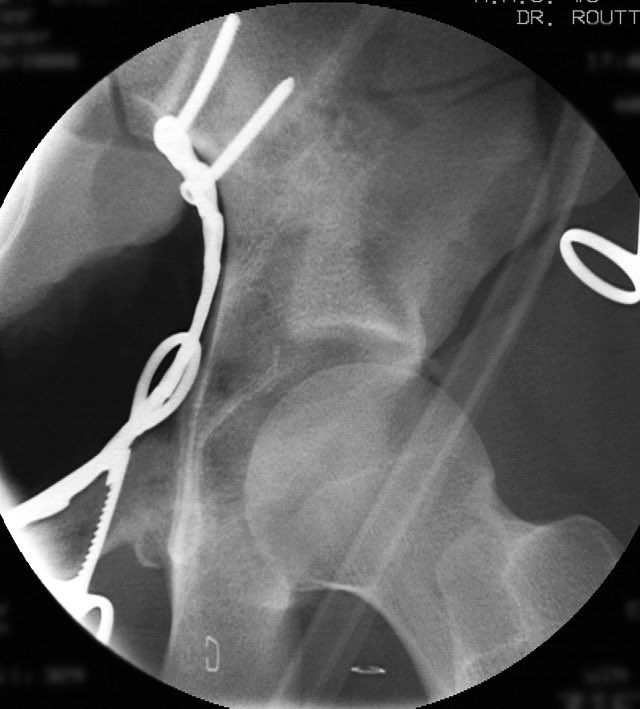

We used a regular table and an Ilioinguinal exposure to first reduce and stabilize the PC fragment to the intact ilium

Then reduced and clamped and stabilized the dome AC fragment

Then finished up the rest